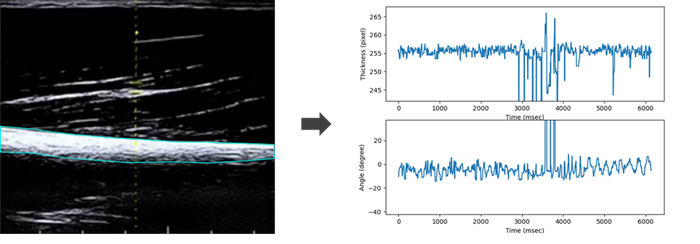

Ultrasound Modalities: Compared B-mode imaging and PW Doppler Imaging for dynamic muscle motion capture. Developed image-processing pipelines in Python using Canny edge detection and wavelet-based feature extraction to convert spectral Doppler velocity traces into time-series signals.

Initial tests using B-mode ultrasound images showed limited accuracy for motion recognition. During experimentation, I discovered that Pulsed-Wave Doppler signals produced distinct patterns for each task. Leveraging this, I trained KNN and LSTM models using Doppler features, showing that ultrasound velocity data can effectively classify upper-limb motions and enhance exoskeleton control precision.

Feature Selection: Applied Discrete Wavelet Transform to obtain 16 time-frequency features. Window segmentation for temporal modeling.